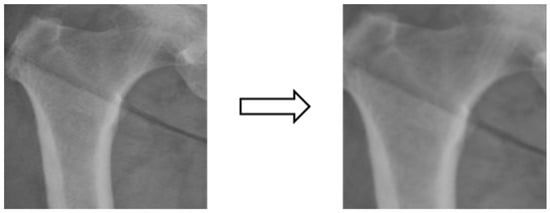

Based on the four parts of the image segmentation of the binary image and the original X-ray image together, the original X-ray image only retains the part of the image segmentation as shown in Figure 4; the other non-part of the contour of the background is removed, and the image is de-behind in the hope that it can enhance the accuracy of the classification of the depth of the learning process, and then the image classification will be segmented images and not segmented images will be compared.

Figure 4. Image matting.